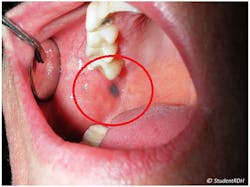

Here is an example of how you might chart the lesion seen in Figure 1.

- Location: behind the patient’s right-side first molar, on the buccal mucosa, above the occlusal plane

- Distribution and definition: single, localized, and well-circumscribed

- Size: 8 mm diameter

- Shape: round macule

- Color: black/blue

- Consistency: soft, similar to surrounding tissues

- Texture: smooth

- History: Patient found the lesion two weeks ago. She reports no history of trauma. No other significant findings on the medical and dental histories.

This oral lesion turns out to be an amalgam tattoo, which is harmless and usually does not develop into cancer. But before arriving at that conclusion, you should chart all the findings and properly store the records. Whenever the patient comes back, you should examine the oral lesion and note any changes.